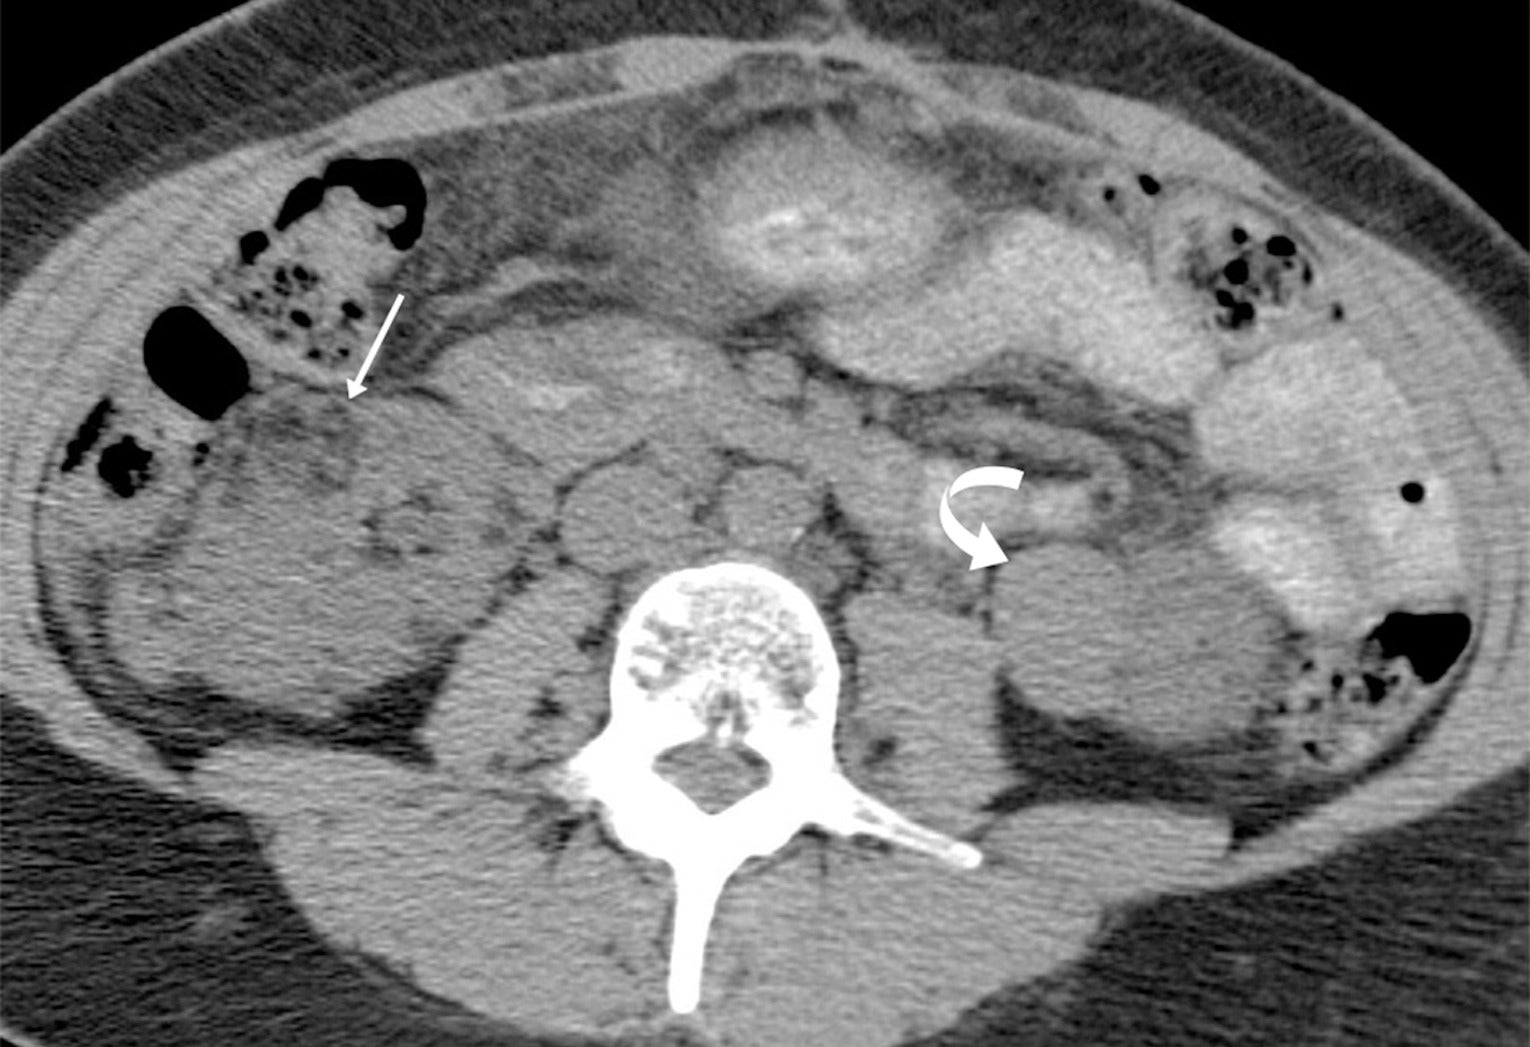

Angiomyolipomas (AMLs) on CT. Adult with tuberous sclerosis and multiple AMLs, most of which are classic with macroscopic fat (arrow) in the right kidney, but hyperattenuating fat-poor AML (curved arrow) in the left kidney.

TS is a genetic disorder characterized by the presence of noncancerous tumors in multiple organs. Renal AML, usually the classic, fat-containing type, occurs in up to 75% of patients with TS. These tumors, which may occur at any age, are often multiple and bilateral ( Figure 3 ) and tend to enlarge with age ( Figure 4 ). Nonclassic subtypes, including fpAML, AML with epithelial cysts, and epithelioid AML, occur more frequently in TS than sporadic AML.4, 5 Close follow-up may be indicated. AMLs in TS tend to be larger and hemorrhage more frequently, necessitating treatment, often with catheter-based interventions for larger tumors (>4 cm) or those that have hemorrhaged.